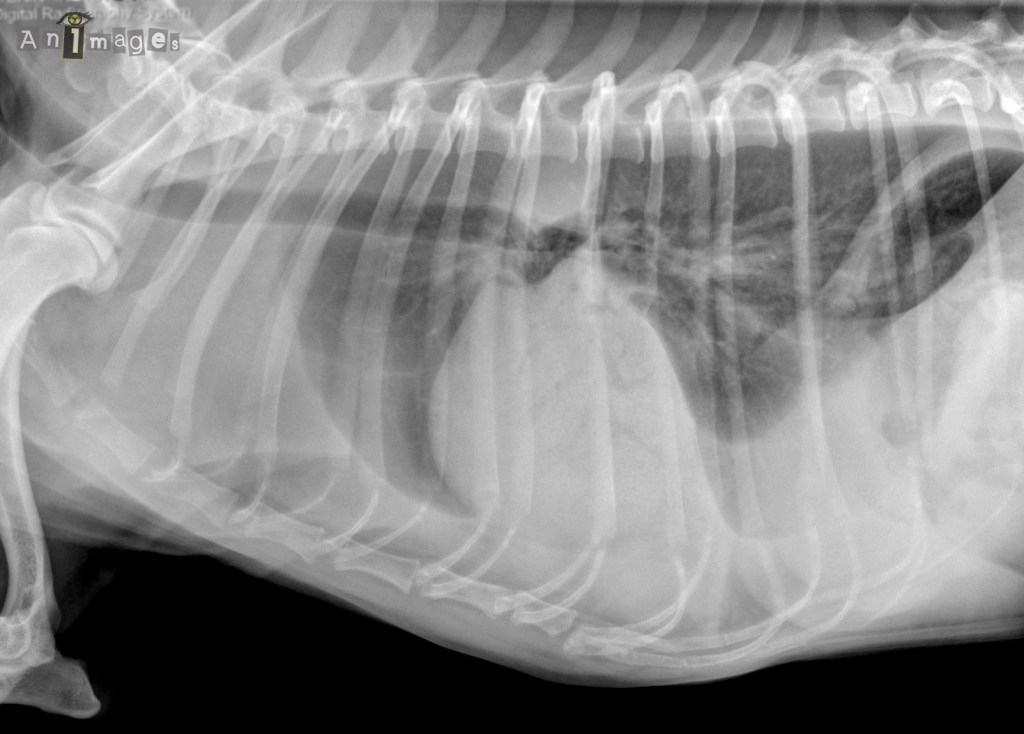

animages_latG

latérale gauche